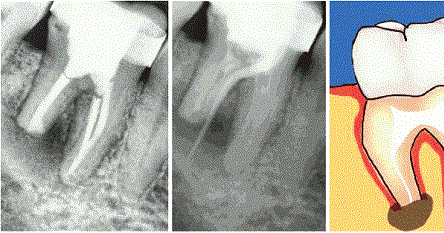

Dis Apsesi Dis Estetigi Gulus Tasarimi Dr Dt Omer Bayar

Dis Apsesi Doktor Amcam